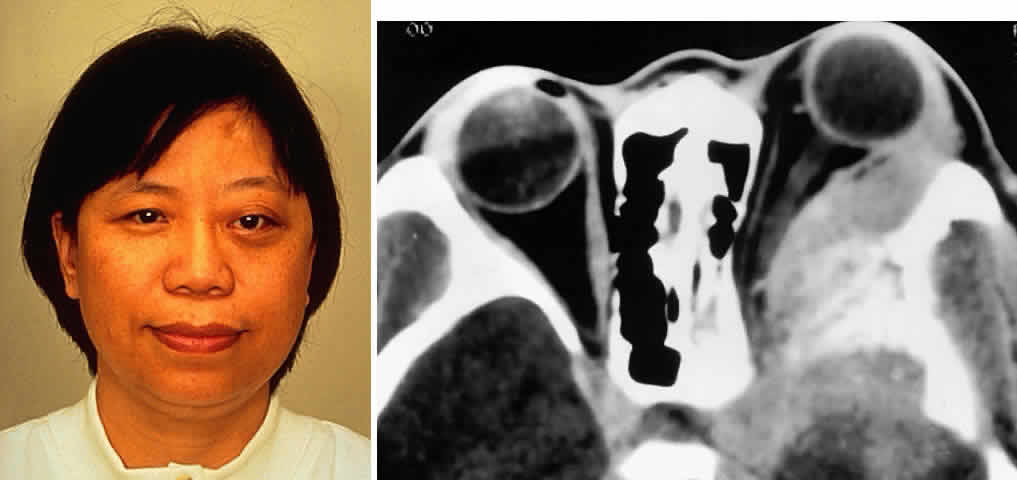

Fig. 5. A 48-year-old Chinese woman had undergone previous frontotemporal craniotomy and partial excision of a left sphenoid wing meningioma. She presented 6 years later with progressive proptosis, visual loss, and numbness of the left cheek and upper teeth that developed during the preceding 2 years. On external examination, she had fullness of the temporalis fossa, an axial proptosis of 11 mm, and downward displacement of the left globe 2 mm (A). Ocular ductions were moderately restricted in all fields of gaze. She had no light perception, marked optic disc pallor, and an optociliary shunt vessel. CT scan revealed an extensive regrowth of meningioma involving the sphenoid wing, with soft tissue components in the temporalis and middle cranial fossae, parasellar region, and orbit, shown here on axial view (B). The lesion also involved the cavernous sinus and pterygopalatine fossa. She underwent a combined resection via the frontotemporal orbitozygomatic approach, followed by radiotherapy (50 Gy in 25 fractions over 5 weeks) for residual components in the cavernous and sphenoid sinuses. Two years after surgery, she remains comfortable and without radiographic evidence of tumor regrowth. Proptosis was reduced to 1 mm axially.